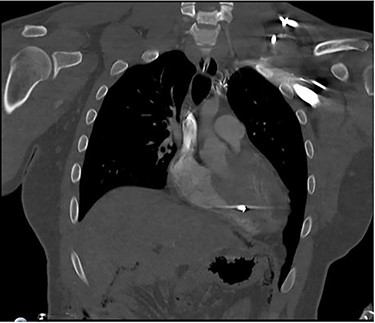

A 25-year-old male presented to the emergency department with four gunshot wounds to the right hip, right flank, left flank and left posterior thorax. Upon arrival the patient was hemodynamically stable with a Glasgow coma score of 15. Chest and abdominal plain films demonstrated a left-sided hemothorax, scattered bullet fragments within the left hemithorax and multiple bullet fragments in the abdominal cavity. A left tube thoracostomy was placed yielding immediate output of 575cc sanguineous fluid and the patient was taken for an exploratory laparotomy. A left diaphragmatic defect was identified with splenic herniation into the left thorax. Splenectomy and primary diaphragmatic repair were performed. Multiple bowel injuries were encountered necessitating several segmental resections. The next day a computed tomography (CT) scan of the chest, abdomen and pelvis was obtained, which identified presence of two bullet fragments in the interventricular septum (Figs 1 and 2).

Coronal CT scan of the chest identifying bullet fragment in the interventricular septum.